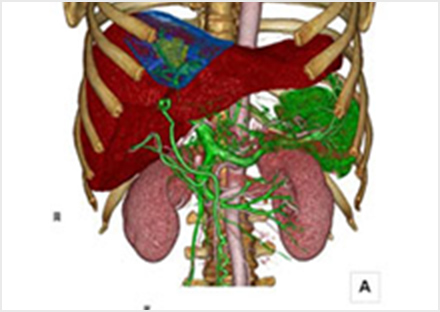

CT・MRI・アイソトープ検査の画像診断を主に行っています。画像を専門とする立場から臨床現場へと医療情報を提供します。またIVRと呼ばれる、カテーテルを使った検査・治療(肝腫瘍に対するTACE・子宮筋腫に対するUAEなど)を行っています。近隣の医療機関からの紹介患者さんの検査をCT・MRI・アイソトープ検査を中心に行っています。来院された患者さんと直接問診をして検査を受けていただきます。

X線とコンピューターを利用して人体の断面画像を撮影する装置で、全身の臓器の形態診断に不可欠な存在となっています。当院のCT装置はエリアディテクターCTと呼ばれる最新の技術が用いられており、広範囲を短時間に撮影する事ができます。検出器1回転が0.275秒での超短時間ボリュームスキャンでスクリーニング検査から救急・精密検査まで、一度の撮影で多くの情報を得ることが可能です。得られた画像から脳血管や心臓血管・骨などの立体的(三次元)表示・解析も可能となっております。また、造影剤を使用することで、より詳しい検査を行う事も可能です。

血管撮影

血管の中にカテーテルと呼ばれる管を入れて様々な血管の状態を調べる事が可能な検査です。心臓の血管(冠動脈)の検査も行っており、検査の結果次第では、その場で治療を行います。また頭部や腹部では病気のある部分の血管にカテーテルを進めて、そこから薬を注入したり血管を塞栓したりする事により、副作用が少なく効果の高い治療を行うことができます。